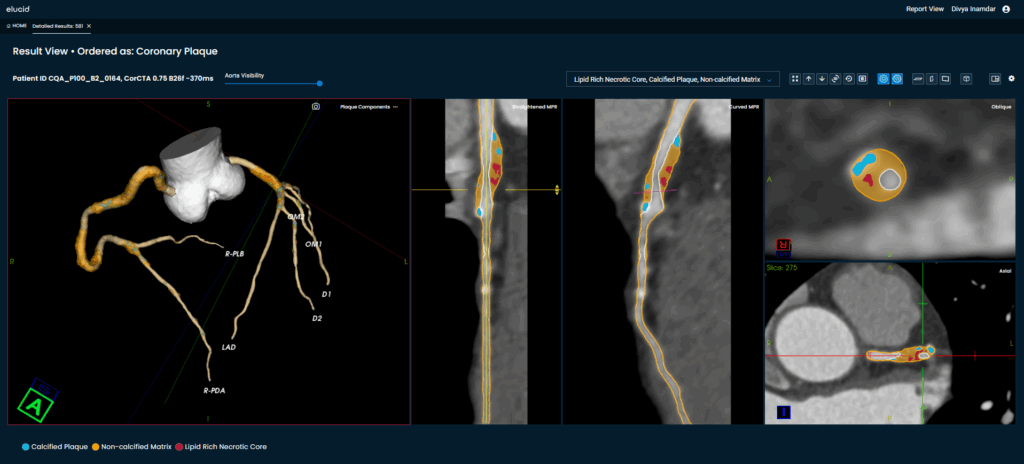

Coronary computed tomography angiography (CTA) with plaque analysis offers invaluable insights into plaque burden, composition, and morphology, enabling earlier and more accurate identification of high-risk patients who may benefit from targeted medical therapy and lifestyle interventions. Numerous studies have demonstrated that such non-invasive imaging enhances risk stratification and clinical decision-making while reducing the need for more invasive and costly diagnostic procedures.